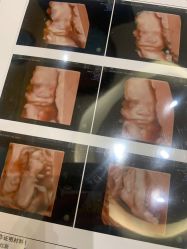

• 杭州贝瑞斯美华妇儿医院·早孕·产检·儿科

肚里圆圆 上传于 23-01-09 | 报错

• -杭州贝瑞斯美华妇儿医院·早孕·产检·儿科